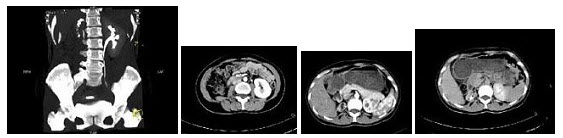

104、多项选择题

女,42岁,左侧腰背部胀痛不适1年余,5年前行左侧卵巢囊肿切除术,CT检查如图所示,下列说法正确的是()

A.左侧附件区可见一囊性肿物,压迫输尿管下段

B.左侧输尿管下端狭窄

C.左侧肾盂肾盏扩张积水

D.左侧输尿管中上段扩张

E.考虑为左侧卵巢囊肿术后复发压迫并粘连输尿管致其狭窄